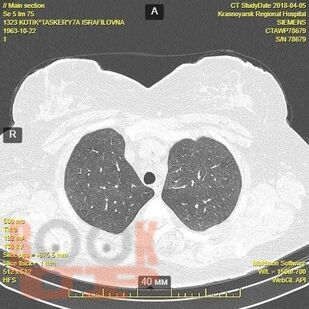

Гранулематозные заболевания легких

Гранулематозные заболевания легких : учебное пособие / И. В. Демко, Н. В. Гордеева, М. Г. Мамаева и др. - Красноярск : КрасГМУ, 2022. - 167 c. - Текст : электронный // ЭБС "Букап" : [сайт]. - URL : https://www.books-up.ru/ru/book/granulematoznye-zabolevaniya-legkih-19634258/ (дата обращения: 17.04.2026). - Режим доступа : по подписке.

Учебное пособие предназначено для врачей общей практики, участковых терапевтов, аллергологов, пульмонологов. В настоящем учебном пособии освещены принципы ведения пациентов с диссеминированными заболеваниями легких. Обсуждаются вопросы этиологии, патогенеза, диагностики, а также основные методы лечения.